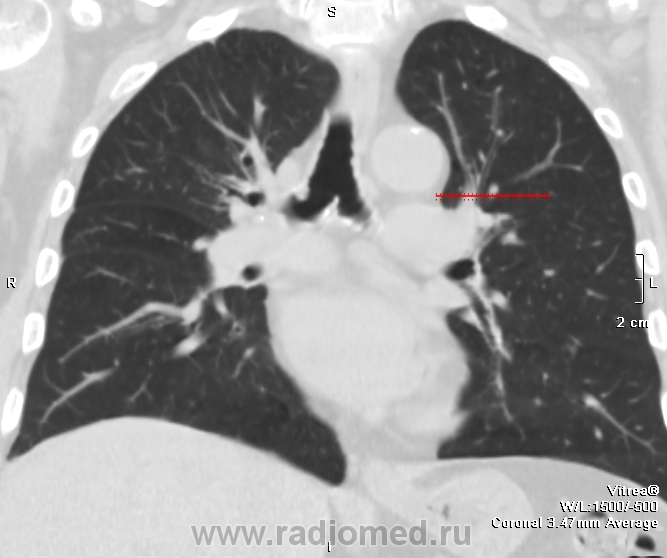

В процессе описания возникли сомнения о природе образования решили дообследовать - динамика на след день (Единичный очаг в н/д слева был и ранее. У больного сильный влажный кашель и обильное отхождение мокроты, вот такие вот дела.

Я правильно понимаю, что эндобронхиальных образований минимум 2?

имеющее обсуждение образование одно в области правого главного бронха.. явственно эндобронхиального происхождения.. но что мешает придраться к аксиальным срезам с перитрахеальной ненормальной плотностью?..

Вношу ясность: тут два исследования - первое исследование сделано в понедельник, второе во вторник - в просвете бронха имеет место что то симулирующее tr, что было на верхней стенке, а затем переместилось на нижнюю за сутки - слизь.